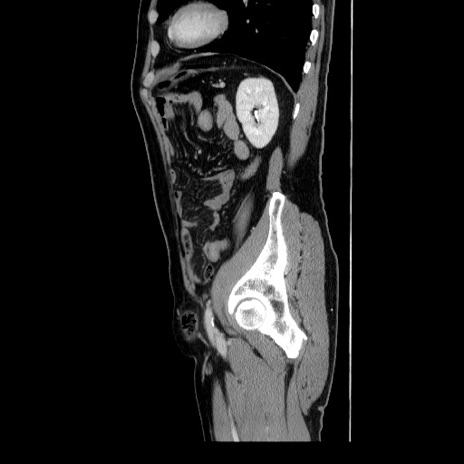

症例34(矢状断像)

【症例】60歳代 男性

【主訴】右鼠径部膨隆

【現病歴】1年程前より右鼠径部膨隆あり。自己にて還納可能だったため放置していた。3時間前より右鼠径部の脱出を認め、還納困難となり受診。

【身体所見】右鼠径部に小児頭大の膨隆あり。弾性硬であり、用手還納は困難。左鼠径部にも膨隆を認める。脱出はなし。